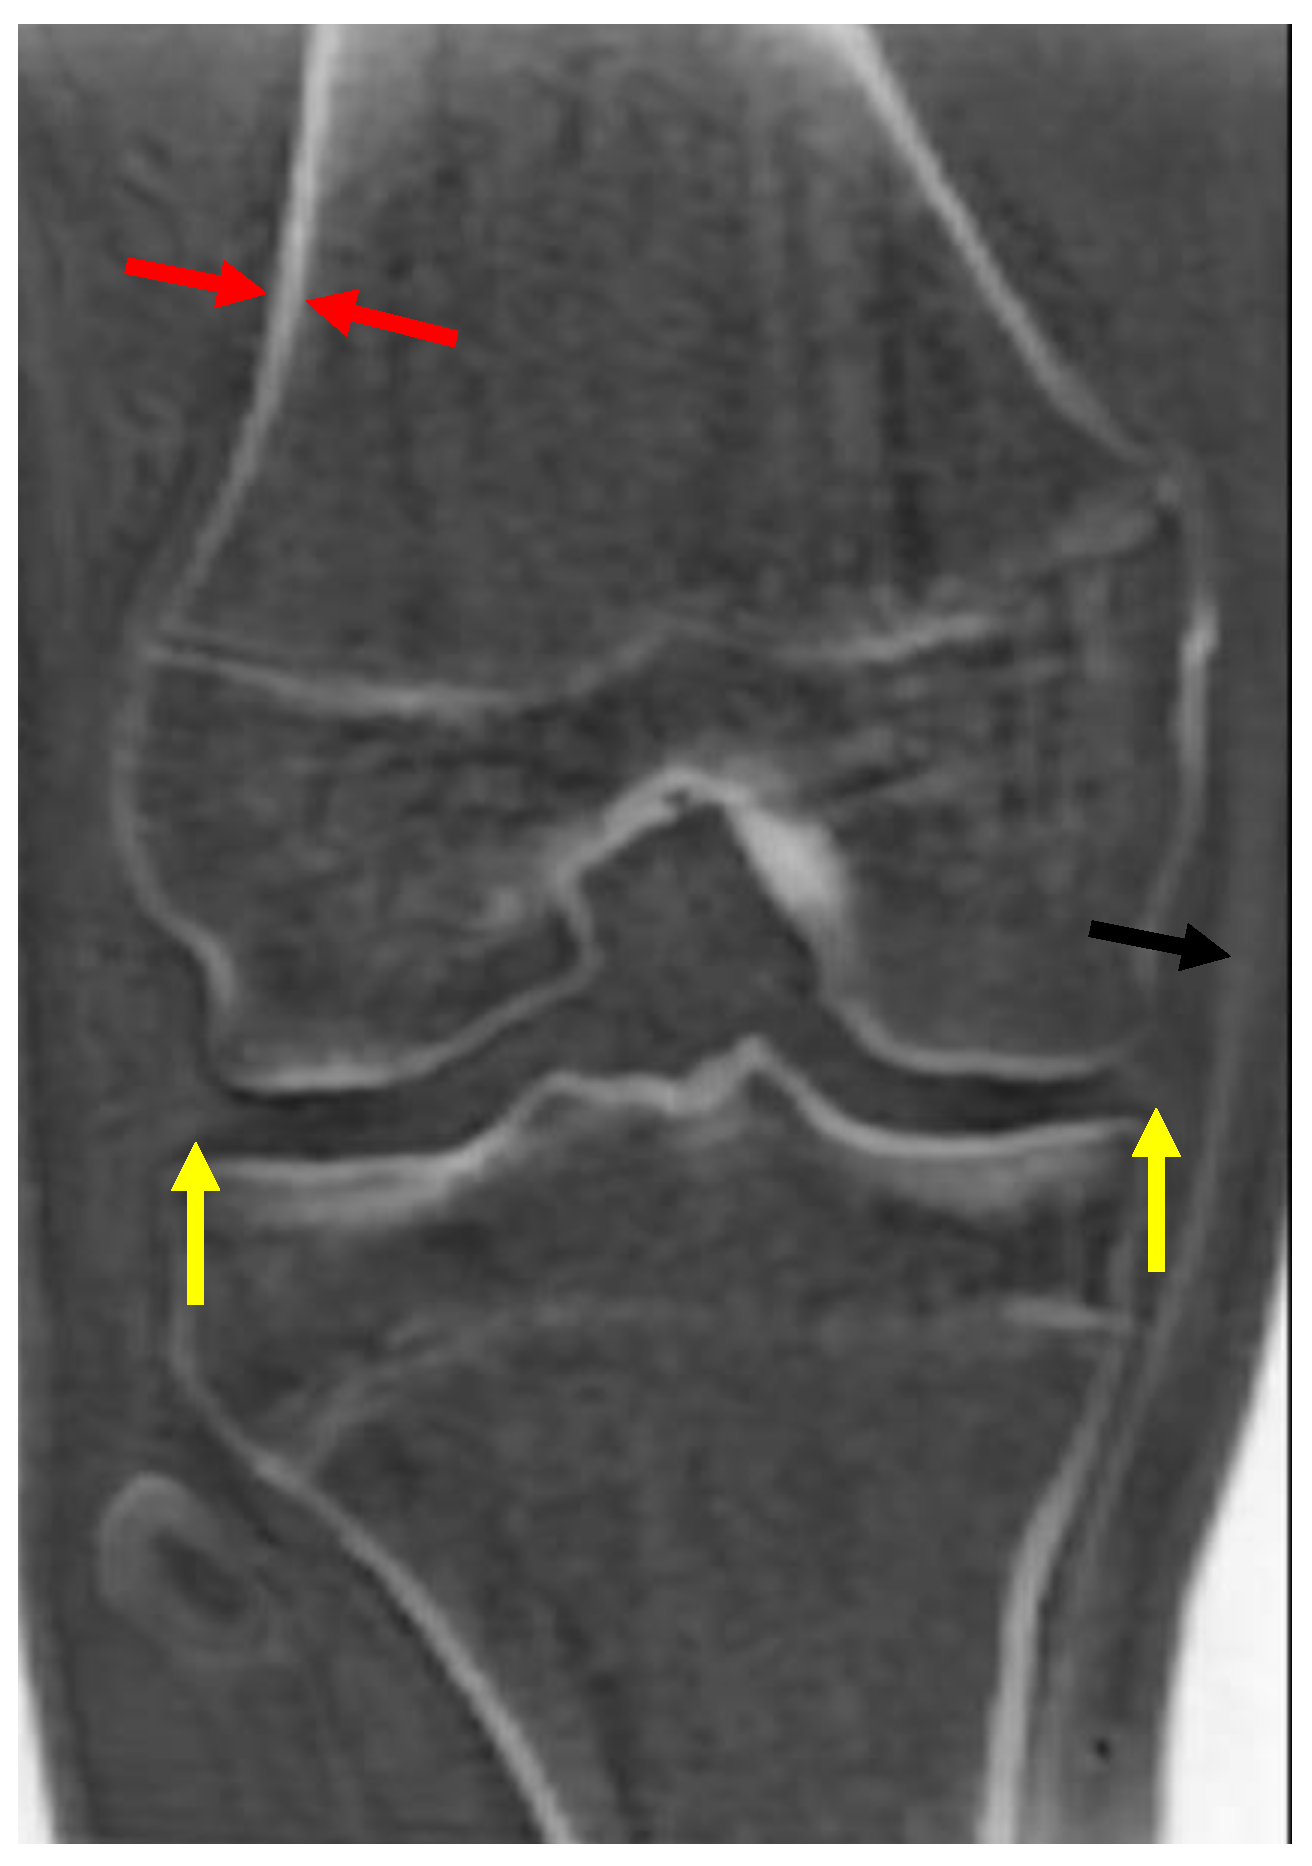

Figure 1.

Coronal zTE image of the knee displayed with an inverted gray scale. Cortical bone (red arrow) is bright. Other short T2 tissues, such as the medial collateral ligament (black arrow) and the menisci (yellow arrows), are also bright, but less so than the cortical bone.